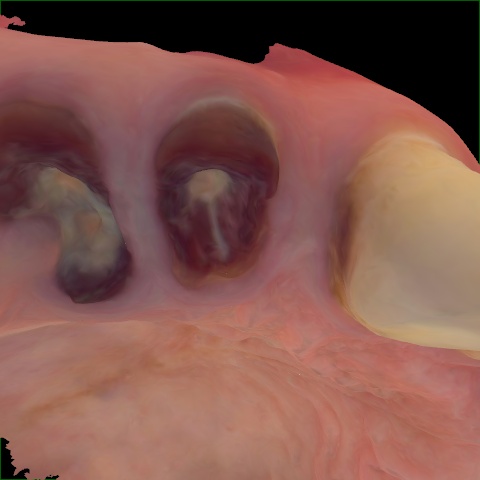

Image 1259 / 1743

NHD36692

Annotated as "Good"

Original Image Rendering Image